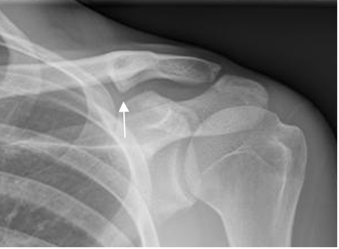

Fig 38. Fractura de clavícula.

Rx AP. Fractura consolidada con callo óseo hipertrófico, en la parte inferior.